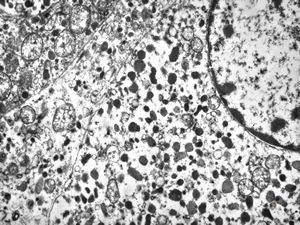

M, 49y. | pancreatic tumor (insulinoma v.s.)